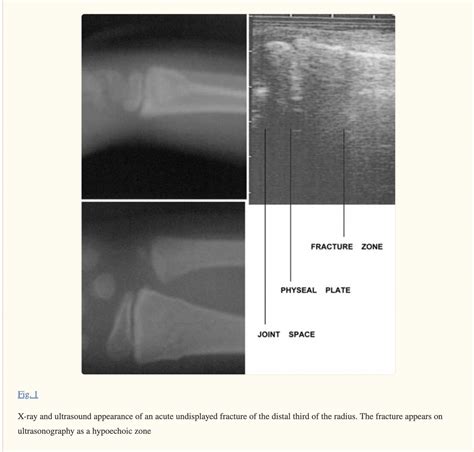

• Order imaging tests, such as X-rays, to confirm the diagnosis and determine the extent of the fracture.

X-rays are the primary imaging tool used to diagnose a Buckle Fracture Radius. They provide a clear view of the bone and can show the characteristic buckling or compression of the bone.